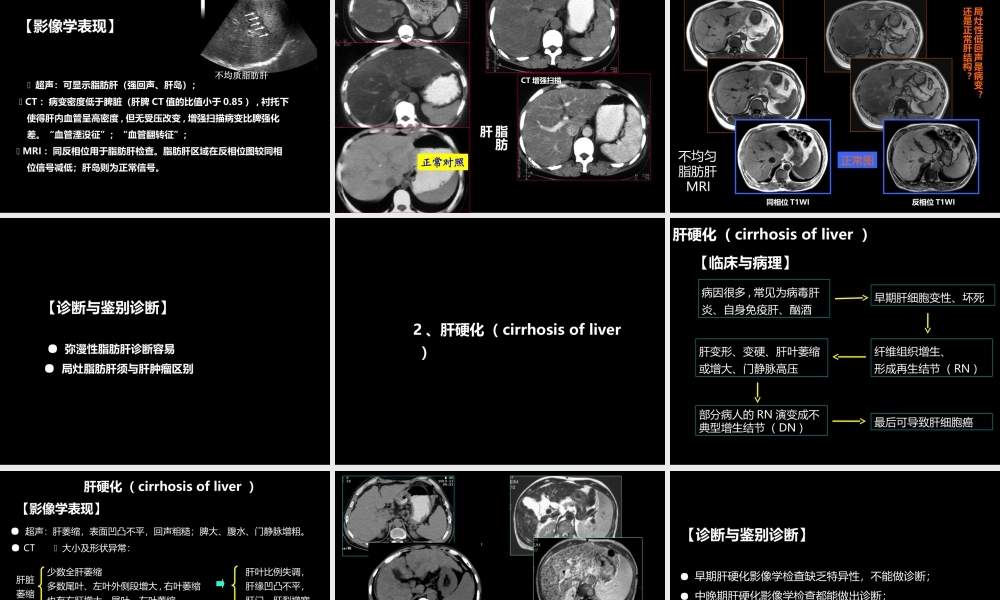

肝胆胰影像学诊断中国石油中心医院影像学教研室杨景震(X线、超声、CT、MRI)注:使用幻灯放映模式浏览2014-10修改版肝脏1、X线平片:很少应用;肝脏血管造影:很少用于诊断,更多的用于介入治疗2、超声检查:常用的检查方法3、CT检查:主要的检查手段之一⑴平扫⑵增强:多期增强;动态增强;CT灌注(一)检查技术4、MR检查:一般认为是在超声检查或CT检查之后的检查。用于疾病的鉴别或早期癌灶的检查与诊断(1)平扫:多种成像序列,用于获得更多的信息(2)增强:多期增强,使用Gd-DTPA.(3)使用特殊对比剂:2类:超顺磁性氧化铁,被肝内网状内皮系统的Küpffer细胞吞噬,据此可推断病变内是否有此种细胞。另一类为肝细胞特异性对比剂(如钆塞酸二钠),被肝细胞摄取、转运,可用于肝细胞癌检出。(一)检查技术(二)正常影像表现1、肝脏位置与形态:2、肝脏的大小:超声测量:右叶前后径8-10cm;最大斜径为10-14cm;左叶厚度不超过6cm;长度不超过9cm。3、肝叶、肝段划分:4、肝实质:5、肝血管:1、肝脏位置与形态:2、肝脏的大小:3、肝叶、肝段划分:肝脏分右叶、左叶和尾叶。为适合外科学需要,影像检查根据肝内血管分布特点把肝脏划分为若干肝段。通常以肝右、肝中、肝左静脉作为纵向划分标志,以门静脉左右支主干作为横向划分标志,如此将肝脏划分为八个肝段。4、肝实质:5、肝血管:Couinaud根据肝内门静脉干和肝静脉的分布范围,将肝脏分为八段,门静脉分支分布于肝段内,而肝静脉位于肝段间。具体如下:以肝中静脉所在纵行平面将肝脏分为左右半肝,以肝左静脉为界将左半肝纵行分为左内与左外叶,而左外叶以门静脉左支为界水平分为上下两段,以肝右静脉纵向、门静脉右支横向将肝右叶分为上下前后四段,而肝尾叶为单独的一段,即:S1为尾状叶,S2为左外叶上段,S3为左外叶下段,S4为左内叶,S5为右前叶下段,S6为右后叶下段,S7为右后叶上段,S8为右前叶上段。1、肝脏位置与形态:2、肝脏的大小:3、肝叶、肝段划分:4、肝实质:超声肝实质均匀一致中等回声;CT为高于脾脏密度(CT值:55-75HU),其中血管为圆形或管状低密度。多期增强肝实质动脉期强化不明显,门静脉期强化开始明显,于平衡期强化达到高峰;MRI检查,肝实质信号均匀,其信号在T1WI高于脾脏,T2WI低于脾脏。多期增强特点同CT。1、肝脏位置与形态:2、肝脏的大小:3、肝叶、肝段划分:4、肝实质:5、肝血管:肝动脉、门静脉由肝门入肝;肝静脉于第二肝门汇入下腔静脉。(1)DSA:不同...